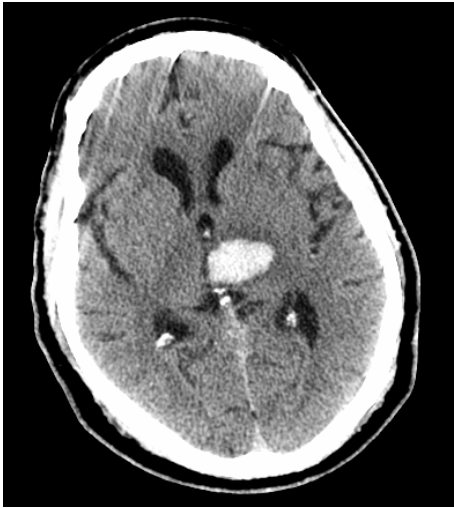

**Case 8 Q# 1 of 3** * 19 y/o man collapsed playing basketball. He was having a seizure consisting of right arm shaking and then fell to the ground without protecting himself. * On arrival noted to have weakness on his right side, reactive pupils, positive corneals and cough. Not following commands or moving spontaneously. * Vitals: 220/120, HR 45, RR 12 (intubated) * CT is attached What about the CT helps you **rule out** contusion secondary to his fall as the cause of his lesion?

The lesion is **located** in the middle of the cortex. Contusion damage typically occurs around the **frontal pole, occipital pole, or temportal tips** of the brain

**Case 8 Q# 2 of 3** * 19 y/o man collapsed playing basketball. He was having a seizure consisting of right arm shaking and then fell to the ground without protecting himself. * On arrival noted to have weakness on his right side, reactive pupils, positive corneals and cough. Not following commands or moving spontaneously. * Vitals: 220/120, HR 45, RR 12 (intubated) * CT is attached Looking at his CT, what is the underlying brain lesion that has now ruptured to cause his seizure?

Arteriovenous malformation (AVM)

**Case 8 Q# 3 of 3** * 19 y/o man collapsed playing basketball. He was having a seizure consisting of right arm shaking and then fell to the ground without protecting himself. * On arrival noted to have weakness on his right side, reactive pupils, positive corneals and cough. Not following commands or moving spontaneously. * Vitals: 220/120, HR 45, RR 12 (intubated) * CT is attached What further brain injury is this man at imminent risk for? How can you tell?

**Brain Herniation**. **Extreme HTN + low HR = Cushing Reflex**, which is noted in patients with increased ICP and can suggest imminent herniation.